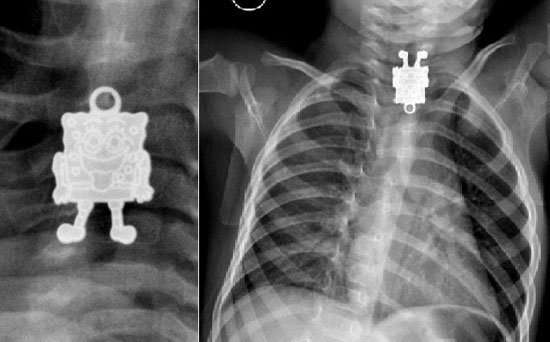

استخرج أطباء لعبة “سبونج بوب” الكارتونية الشهيرة من مرئ رضيع بعد أن استقرت فيه وكادت تودي بحياته لولا التدخل الجراحي.

ونجح الأطباء بمستشفى الملك عبدالعزيز في السعودية في استخراج سبونج بوب من مريء الرضيع البالغ من العمر 16 شهراً.

وأحضر أب طفلهُ الرضيع إلى المستشفى، مخبراً عن أنه ابتلع قطعة غير معروفة، وبإجراء الأشعة فوجئ الأطباء بوجود بوجه سبونج بوب يبتسم لهم في الاشعة السينية ما أصابهم للوهلة الأولي بالدهشة.

وفوراً أجرى الأطباء جراحة للطفل لاستخراج القطعة قبل أن تسبب تهديداً لحياة الرضيع.

و نشرت إحدى أخصائيات الأشعة بمستشفى الملك عبدالعزيز صوراً للأشعة السينية ويظهر فيها سبونج بوب، مشيرة إلى أنها للوهلة الأولى بعد اطلاعها على الصورة الجانبية ظنت أن الطفل ابتلع قلماً، إلا أنها تفاجأت بعد ذلك من الصور الأمامية بأنها قلادة على شكل “سبونج بوب”.